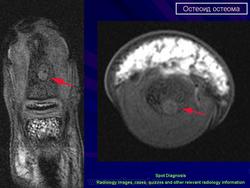

МРТ. Внутрисуставная остеоид остеома

(а) МР изображение фиксирует очаг - стрелка в шейке правой бедренной кости с окружающим отеком (*) костного мозга. Имеет место некоторое количество выпота.

(б) МР изображение (с гадолинием) регистрирует очаг - стрелка и интенсивный синовиальный компонент - наконечники стрел.

(б) МР изображение – очаг с низким уровнем «сигнала», с центральным очагом - стрелка.